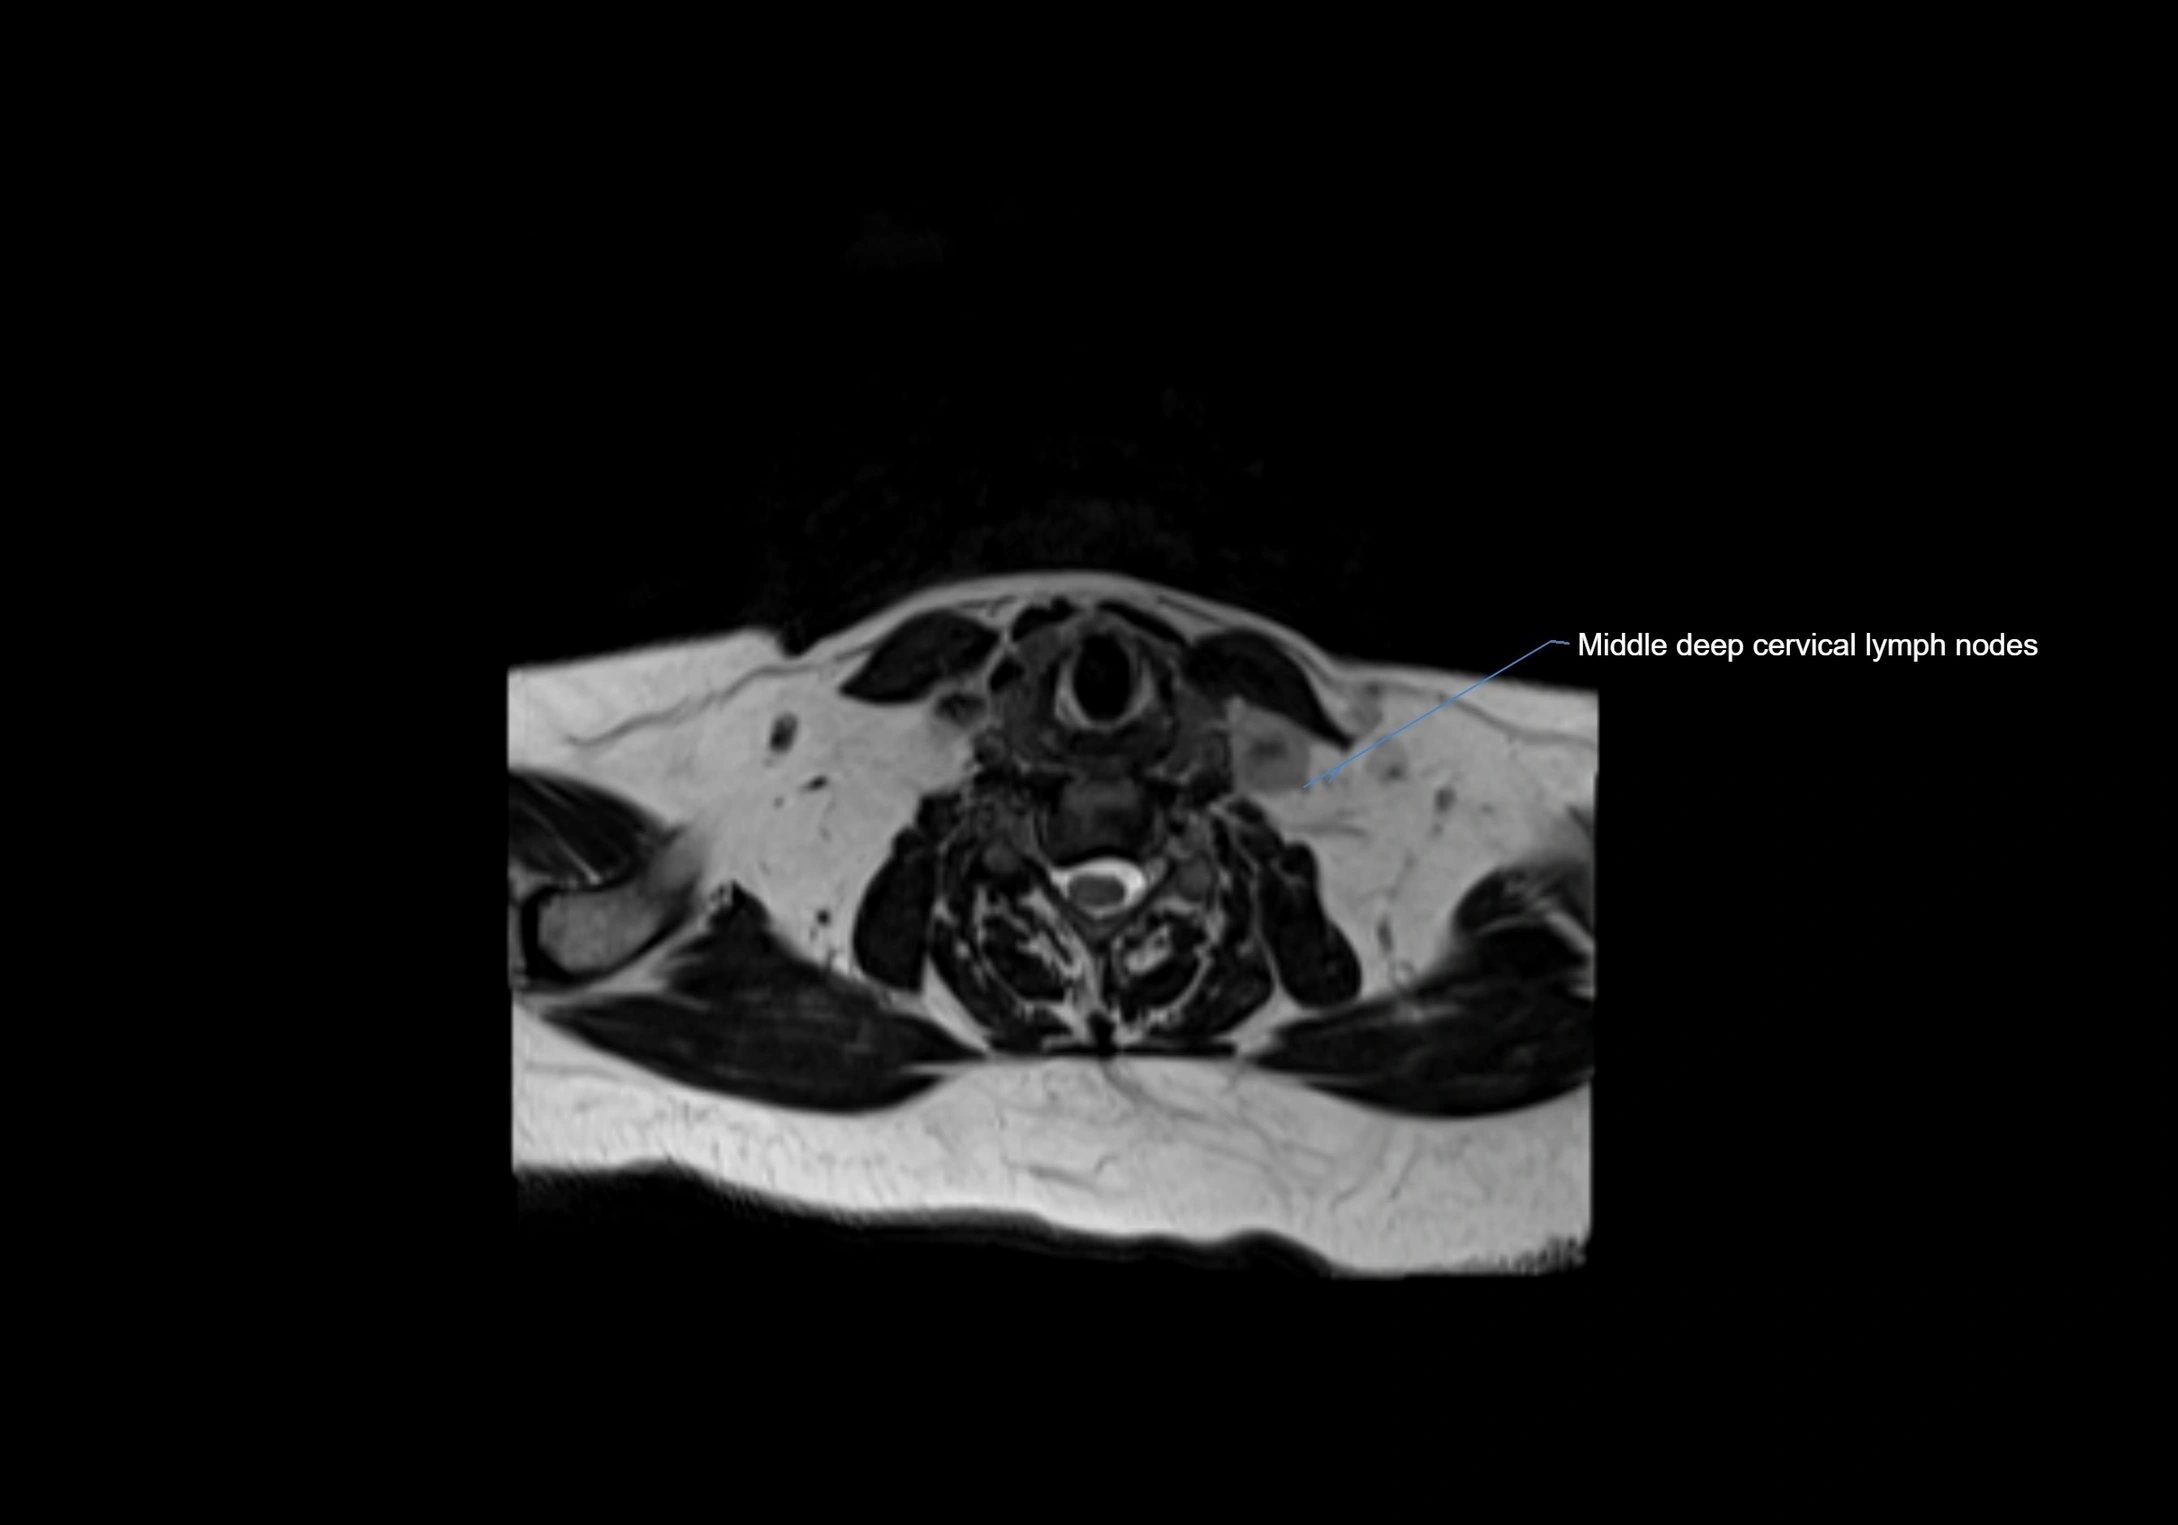

MRI Appearance

T1-weighted images:

• Normal accessory nodes appear as small, oval hypointense to intermediate signal structures within subcutaneous fat

• Surrounded by hyperintense fat, enhancing contrast for visualization

• Pathological nodes may appear enlarged or rounded, sometimes with cortical thickening

T2-weighted images:

• Nodes show intermediate signal, with surrounding fat bright

• Useful for detecting edema, inflammation, or infiltration

• Fatty hilum may appear slightly hyperintense relative to cortex

CT Appearance:

• Nodes appear as small, soft tissue density structures embedded in subcutaneous fat near primary lymph nodes

• Surrounded by air in adjacent facial cavities or normal soft tissue, providing natural contrast

• Enlarged or pathological nodes appear as well-defined or irregular soft tissue masses

• CT is particularly useful for preoperative assessment, infection evaluation, or detection of metastatic spread

MRI images